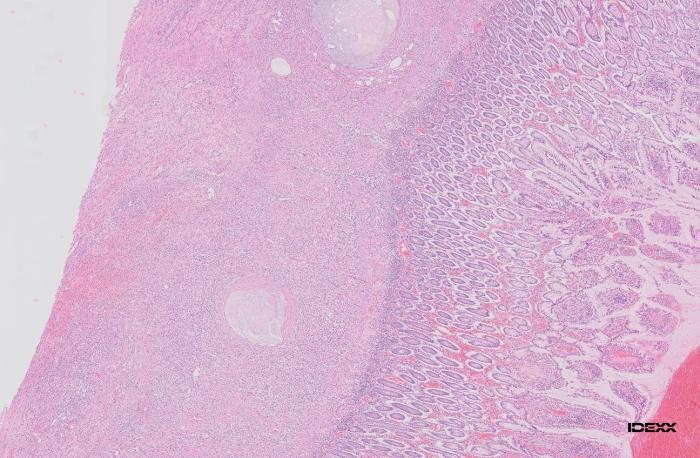

Histopatológicamente, la zona de engrosamiento intestinal se caracterizó por un intenso infiltrado de neutrófilos, macrófagos y, en menor medida, linfocitos y células plasmáticas, que afectaba predominantemente a la mucosa y se extendía al tejido muscular y mesenterio adyacente. Este proceso inflamatorio se acompañaba de hemorragia abundante y leve reacción de fibroplasia. Multifocalmente, se observaron pequeños agregados de macrófagos espumosos y ocasionales células gigantes multinucleadas dispuestos alrededor de espacios de contenido eosinofílico anfofílico pálido, correspondientes a vasos linfáticos dilatados bordeados por una fibroplasia concéntrica leve. Lesiones similares se identificaron también en la submucosa de las zonas marginales, no pudiéndose descartar, por lo tanto, la afectación de otros segmentos intestinales. La mucosa restante mostró hiperplasia moderada del tejido linfoide asociado a mucosa y un infiltrado inflamatorio mixto, compuesto por un número moderado de neutrófilos, linfocitos y células plasmáticas. Estos hallazgos fueron consistentes con linfangitis lipogranulomatosa focal grave (Figura 3A-D).

Figura 3A-D. Histopatología intestinal que evidencia linfangitis lipogranulomatosa focal grave, con infiltrado inflamatorio mixto, hemorragia, fibroplasia leve y dilatación de vasos linfáticos con macrófagos espumosos y células gigantes multinucleadas.